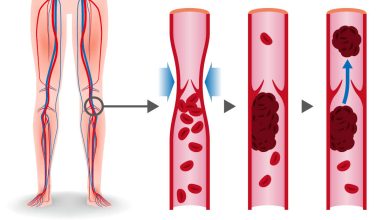

- قد يصاب الشخص بمرض فقر الدم وإنخفاض في عدد كرات الدم الحمراء .